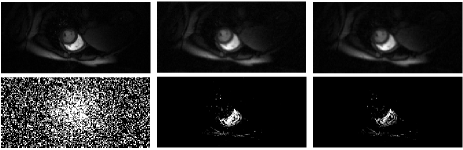

In Fig.1, we compare the recovery results of the TMNN with MNN on a cine cardiac MR image from 30 radial lines (undersampling ratio 0.1) in the noiseless case. We observe that the proposed TMNN model outperforms the MNN method in providing more accurate reconstruction. Fig.2 shows the reconstruction of the cine cardiac MR image from the noisy undersampled measurements using 30 radial lines. In Fig.3, we plot the noisy reconstruction results of the perfusion MR image from the variable density random sampling trajectory with the undersampling ratio of 0.3. It is observed that the TMNN method generates less error compared with the MNN approach. The SNRs of the reconstructed dynamic image using TNN, MNN, and the proposed TMNN at different undersampling conditions are shown in Table.1. We observe that except for one case, the proposed TMNN consistently provides the best reconstruction results and improves the SNR by up to 2dB over the MNN method. In addition, it is shown that the improvement of the proposed TMNN over MNN is more significant in the noisy setting.

Fully sampled MNN recovery TMNN recovery